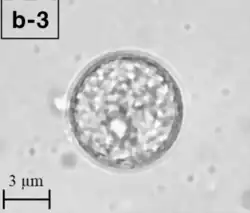

A Balamuthia mandrillaris cyst

B. mandrillaris is a free-living, heterotrophic amoeba, consisting of a standard complement of organelles surrounded by a three-layered cell wall (thought to be made of cellulose or a similar polysaccharide[8]), and with an abnormally large cell nucleus. On average, a Balamuthia trophozoite is about 30 to 120 μm in diameter. The cysts fall around this range, as well.[9]

Balamuthia's lifecycle, like the Acanthamoeba, consists of a cystic stage and a non-flagellated trophozoite stage, both of which are infectious, and both of which can be identified in the brain tissue on microscopic examination of brain biopsies performed on infected individuals. The trophozoite is pleomorphic and uninucleated, but binucleated forms are occasionally seen. Cysts are also uninucleated, possessing three walls: an outer thin irregular ectocyst, an inner thick endocyst, and a middle amorphous fibrillar mesocyst.[10]